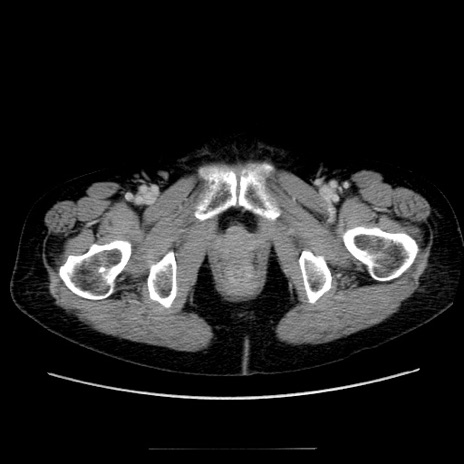

症例5(横断像)

【症例】70歳代女性

【主訴】お腹が張る

【現病歴】1週間くらい前から腹部膨満の自覚あり。昨日夜から増悪したため、本日救急外来受診。

【身体所見】意識清明、BT 36.5℃、BP 165/106mmHg、HR 80bpm、SpO2 98%、腹部:膨満、軟、自発痛・圧痛なし、触診にて不快感あり、腸蠕動音:減弱

【データ】WBC 12600、CRP 1.04